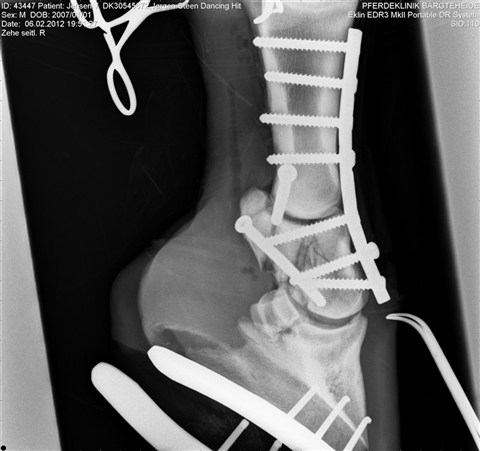

On the tragic news front - Dressage Royal's grandson ERA Dancing Hit (by UNO Don Diego) broke his pastern during a lounging session on Monday. The full story can be found HERE. If you are having trouble remembering who he is, here's the skinny - a 2008 stallion who won the Danish Licensing by a landslide margin. Apparently, the veterinarians were able to put some pins in, so we wish Dancing Hit and all of his connections the very best during his recovery. This is a LINK to the post surgical radiograph...how tragic!